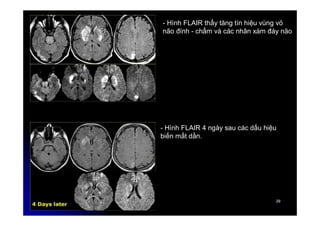

- Hình FLAIR thấy tăng tín hiệu vùng vỏ

não đính - chẩm và các nhân xám đáy não

- Hình FLAIR 4 ngày sau các dấu hiệu

biến mất dần.